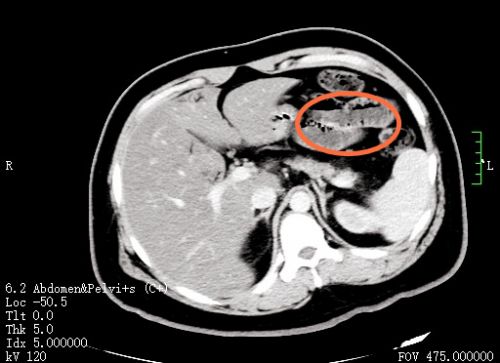

ct显示,肝脏、门静脉、肠壁内都有明显积气(红圈内)。

进入急诊三科抢救室时,小刘已经神志浅昏迷,呼吸急促,脉搏高达145/分,血压低至休克,快速血糖检测高到“爆表”,只得抽血测血糖,结果显示为123.10mmol/L,超出正常值20多倍!此外,感染指标明显升高;腹部 CT显示:左肝静脉、门静脉、肠系膜静脉及小肠壁积气明显,考虑小肠坏死,随即转入急诊重症病房(EICU)。

“门静脉和肠系膜静脉等出现积气是因为产气细菌进入血液,这种情况在影像学上被称为‘死神之征’,死亡率高达50%”,捷克论坛 急诊三科主任张兴文主任医师表示,小刘由于不良生活方式导致体重超标,并患上糖尿病,在此之前一直没有规范治疗和改变不良生活方式,这次因为肠道菌群失调、移位出现肠源性感染,引发感染性休克,最终导致严重的糖尿病酮症酸中毒(DKA),危及生命。